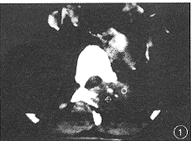

患者男,36岁。腰背部疼痛,颈部不适2个月。因疼痛加重,腰背部出现包块而住院治疗。查体:体温37.5℃,身体消瘦,痛苦病容。T12棘突两侧有直径4cm大小包块,有波动,压痛。T6棘突左侧软组织隆起,压痛。颈部压痛,活动轻度受限,四肢活动及大小便正常。血沉:46mm/h。胸片显示:粟粒型肺结核。颈椎摄片:未见异常。X线片示:T6左侧椎弓根破坏。CT片示:T6左侧椎板、椎弓根骨质破坏,有死骨,且有软组织肿胀影突入椎管(图1)。T12棘突骨质破坏,有死骨,后方皮下有低密度影(图2)。诊断:T6、T12附件结核伴冷脓肿,粟粒型肺结核,颈痛待查。按3HRZS/15HR方案抗痨治疗[1,2](注:H-异烟肼,R-利福平,Z-吡嗪酰胺,S-链霉素)。半个月后,分别行T6和T12经后路结核病灶清除术,清除较多脓液、干酪样物及少量死骨。病理检查:T6、T12结核。术后10余天,颈痛加重,活动受限,吞咽感咽部不适,有发热、出汗,体温38℃。颈椎CT片示:寰椎骨质破坏,有死骨,寰枢关节左右间隙不对称,咽后壁软组织影增宽,食管受压(图3,4)。诊断:寰椎结核伴冷脓肿,寰枢椎半脱位。给予输血、补液等支持治疗后,经口腔行病灶清除术,清除少量脓液、干酪样物及少量死骨。术后继续抗痨治疗,颈托固定。此后,颈痛缓解,精神食欲渐好,血沉降至28mm/h。1个月后,胸前(胸骨柄、双侧第四前肋骨处)、上背部出现包块。胸片显示:粟粒型肺结核,双侧第四前肋内侧骨质破坏(图5)。CT片示:T2棘突骨质破坏消失,有低密度的软组织肿胀影(图6)。诊断:T2棘突结核伴冷脓肿,胸骨柄及双侧第四前肋结核伴冷脓肿。考虑结核杆菌感染未能完全控制,改用3HE1321ThK/21HE1321Th方案[1-3](注:H-异烟肼,E-乙胺丁醇,1321Th-丙硫异烟胺,K-卡那霉素)抗痨治疗半个月后,行病灶清除术,分别清除T2、胸骨及肋骨结核病灶。术后1年随访,患者恢复了日常生活及工作,局部无疼痛,血沉正常,体重由入院时的45kg增加到70kg,再未发现新的结核病灶。

图1CT片显示T6左侧椎板、椎弓根骨质破坏,有死骨,且有软组织肿胀影突入椎管图2CT片显示T12棘突骨质破坏,有死骨,后方皮下有低密度影图3,4CT片显示寰椎骨质破坏,有死骨,寰枢关节左右间隙不对称,咽后壁软组织影增宽,食管受压图5胸片显示粟粒型肺结核,双侧第四前肋内侧骨质破坏图6CT片显示T2棘突骨质破坏消失,有低密度的软组织肿胀影